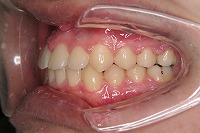

右

反対咬合と下顎が出ている事を主訴に来院された、初診時18歳1か月の男性です。診断「上顎骨の後方位による骨格性反対咬合」非抜歯での矯正治療と、下顎を後退させる外科手術を併用して治療を行いました。